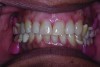

A 63-year-old African-American female presented at the University of North Carolina General Dentistry Student Clinic with a chief complaint that she was missing posterior teeth on both arches and said she would like to replace them (Figure 8).

The patient was concerned about esthetics because she was a school teacher. Her dental history revealed that she had removable partial cobalt chromium dentures that no longer fit and she had not used them for a long period. Her medical history at the initial examination revealed that she had type 2 diabetes mellitus, hypertension, and hyperlipidemia, all of which was controlled. However, she had no medical contraindication for dental care or oral surgical procedures.

The patient was presented with multiple treatment options to address her dental problems, including cast-metal partial dentures, acetal resin flexible partial dentures, and implants to replace the missing teeth and provide a first-molar occlusion. The patient initially opted for implants. During the planning phase for the implant therapy, the patient was hospitalized due to her diabetes and her physician advised against this first choice. Thus, the patient’s treatment plan was modified, and she consented to receiving acetal resin RPDs versus cast-metal RPDs due to her esthetic concerns.

Fig 8. Intraoral pre-operative photograph showing multiple missing posterior teeth in both arches.